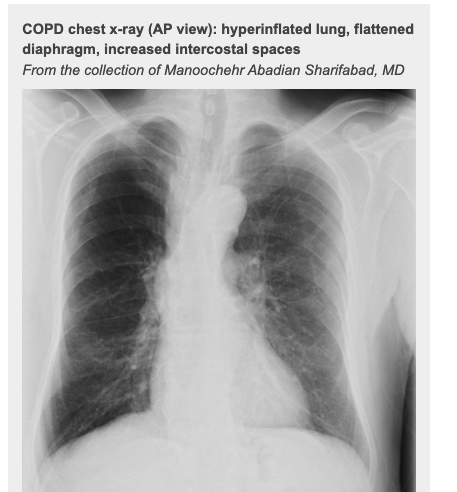

CXR:

- hyperinflation

- bullae

- flat hemidiaphragm